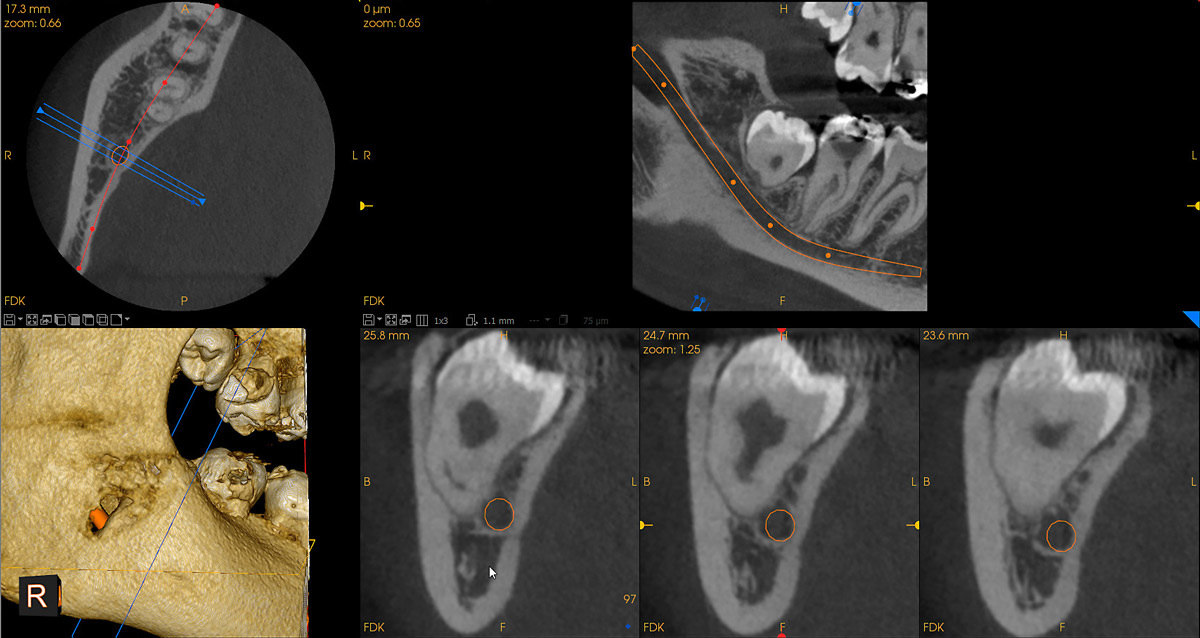

cs9600_5x5_impacted-third-molar

Δημοσιεύθηκε 25 Σεπτεμβρίου 2018 στο 1200 × 638 σε cs9600_5x5_impacted-third-molar